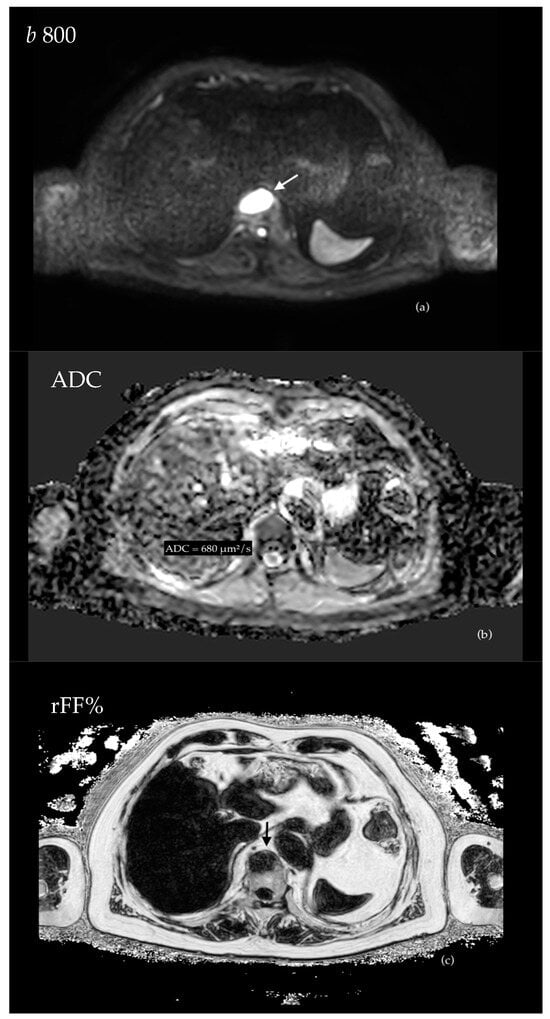

3.4.1. Evaluation of Bone Metastases with WB-MRI

3.4.3. Assessment of Visceral Disease